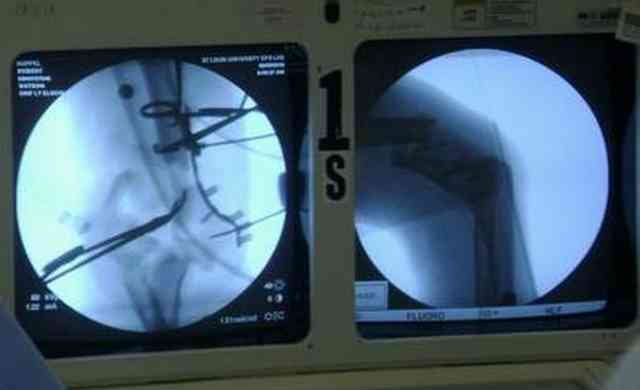

несколько примеров изящной работы ортопедов из СентЛуиса.В первом случае у

политравмированного пациента под ЭОП динамической пробой верифицирован разрыв МБС и

выполнена фиксация позиционными винтами, 3.5 кортикальными. Кстати метчика в работе мы не

видели, все винты self tapping. Во втором случае у пациента с открытым многооскольчатым